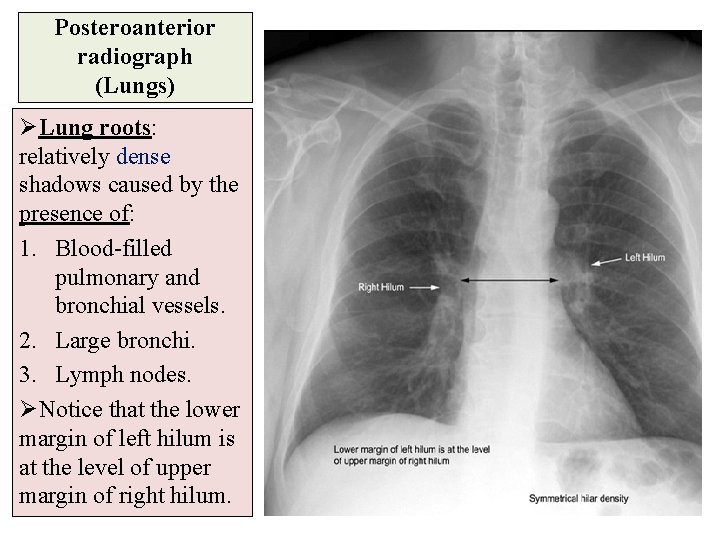

Posteroanterior radiograph (Lungs) ØLung roots: relatively dense shadows caused by the presence of: 1. Blood-filled pulmonary and bronchial vessels. 2. Large bronchi. 3. Lymph nodes. ØNotice that the lower margin of left hilum is at the level of upper margin of right hilum.